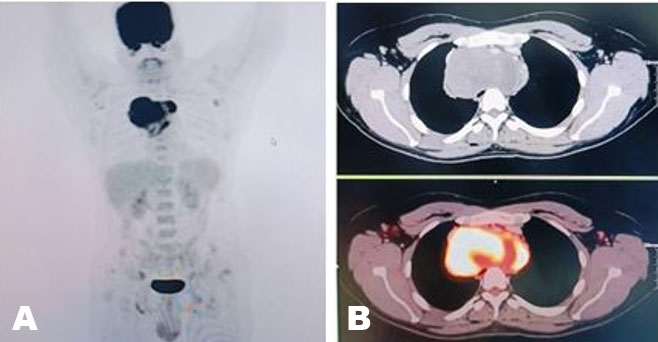

A previously healthy 45-year-old woman was admitted to the hospital for left-sided abdominal pain, significant weight loss of about eighty pounds over seven-month period, along with mild endocrine abnormalities. Pertinent physical exam findings included a large protuberant abdomen with palpable mass occupying the entire left upper quadrant; however, she did not have hirsutism, signs of virilization, or cushingoid features. Initial imaging revealed that she had a large left adrenal mass measuring 24.6 × 21.5 × 17.1 cm, with central necrosis and heterogeneous enhancement (Figure 1 and Figure 2). A 24-hour urinary free cortisol level was 74 μg/24 h, which indicated mild hypercortisolism. DHEAS was elevated at 325 μg/dL, suggestive of androgen overproduction without clinical signs of virilization. The urinary metanephrines were normal and normetanephrines were slightly elevated and measured at 1.5 nmol/L, indicating no evidence of pheochromocytoma. Additionally, the patient exhibited non-PTH-mediated hypercalcemia (total serum corrected calcium 11.4 mg/dL). Skeletal metastasis was ruled out with nuclear medicine bone scan. A multidisciplinary tumor board recommended an en-bloc surgical resection accounting for the size of the mass and radiographic features that were indicative of malignancy. The patient underwent a left adrenalectomy combined with a left nephrectomy, distal pancreatectomy, splenectomy, and extended lymphadenectomy via a chevron incision. The patient’s multiorgan resection successfully cleared the lesion, yielding negative margins and removing 54 lymph nodes, all pathologically negative. This underscores that even with large adrenal masses, nodal spread may be absent if the tumor’s proliferative index is relatively low. Early vascular control near the renal hilum was established to minimize hemorrhagic risk. The surgery was complicated by an estimated blood loss of 2.5 L, requiring intraoperative transfusions. Postoperatively, the patient received stress-dose hydrocortisone to mitigate the risk of adrenal insufficiency. After discharge, the patient was started on external beam radiation therapy for five weeks and identified for long-term surveillance. The patient did not receive adjuvant therapy with mitotane. Subsequent imaging completed three months after completion of radiation therapy revealed no evidence of tumor recurrence. Corrected serum calcium at the same time was 10.0 mg/dL. The patient is currently being closely followed up in the endocrinology clinic for steroid taper.

Figure 2: Resected well-circumscribed tumor.